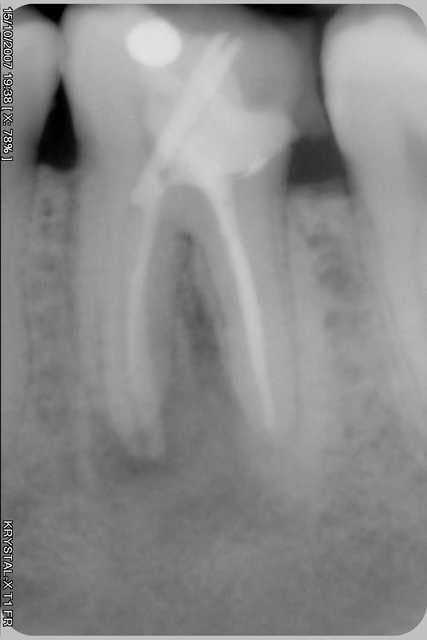

Il s'agit d'une reprise de traitement...

Une idée de ce dont il s'agit...

si tu cherchais l'origine de la fistule, c'est bon tu as trouvé!

si tu parle de la trainé de pate,je crois que l'excedent de pate a du suivre le chemin d'une fistule,c'est le plus plausible a mon sens

bien sur ene telle fusée de pâte c'est pas dans les livres mais en envahissant le trajet de fistule ainsi tu es quasi assuré du succés clinique de ton retraitemet

cela fait un mois que j'ai realisé cette obturation, aucune douleur post op, c'etait mon inquietude. Effectivement c'est bien la fistule que j'ai obturé grace au thermafil mais surtout a un exces de pate probablement. La sortie etait pleine de pate...

Ci-joint la radio a un mois.

PS: je met quand meme un peu moins de pate maintenant.